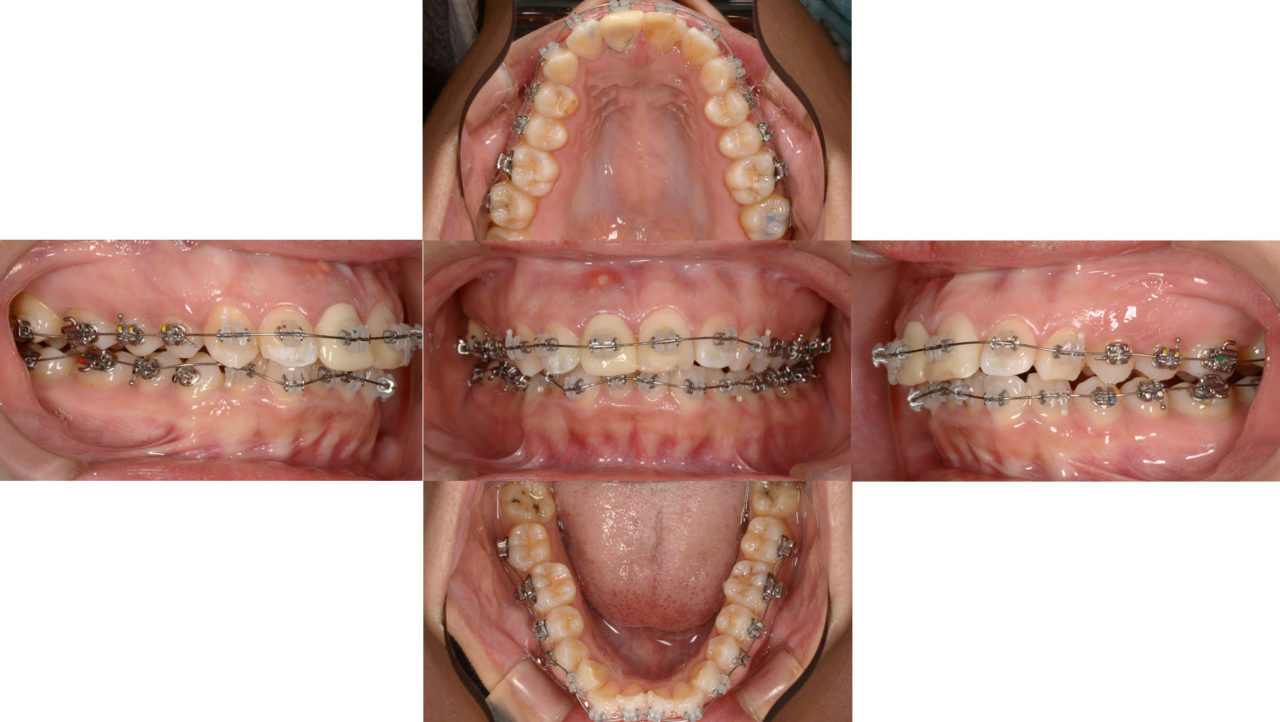

矯正開始 2017.11.27

| 備考 | 以前から気にされていた前歯の被せ物や詰め物の変色は、もちろん改善対象です。 しかし、せっかく美しく治すのであれば、矯正治療で口元全体から美しさを追求しませんか、とご提案しました。 上顎・下顎ともに前歯が大きく前方へ突出しているタイプでしたので、小臼歯を4本抜歯し、前歯を最大限後退させる矯正治療を実施しました。 矯正用アンカースクリューを併用することで、口元を最大限下げることを目指したため、歯の移動距離が大きくなり、治療期間は比較的長くなりました。矯正治療の終了後、前歯2本はセラミックを用いて審美修復を行いました。治療前は口を閉じる際に力が必要でしたが、治療後は口元がすっきりと引き締まりました。 |